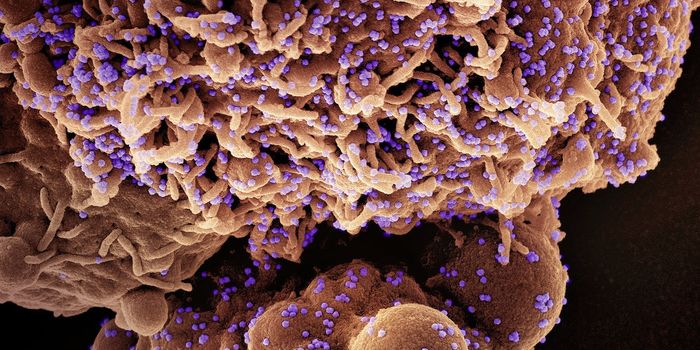

SEP 08, 2021MicrobiologyNipah virus is one of the world's deadliest viruses. It has caused several small outbreaks in Southeast Asia since it em ...